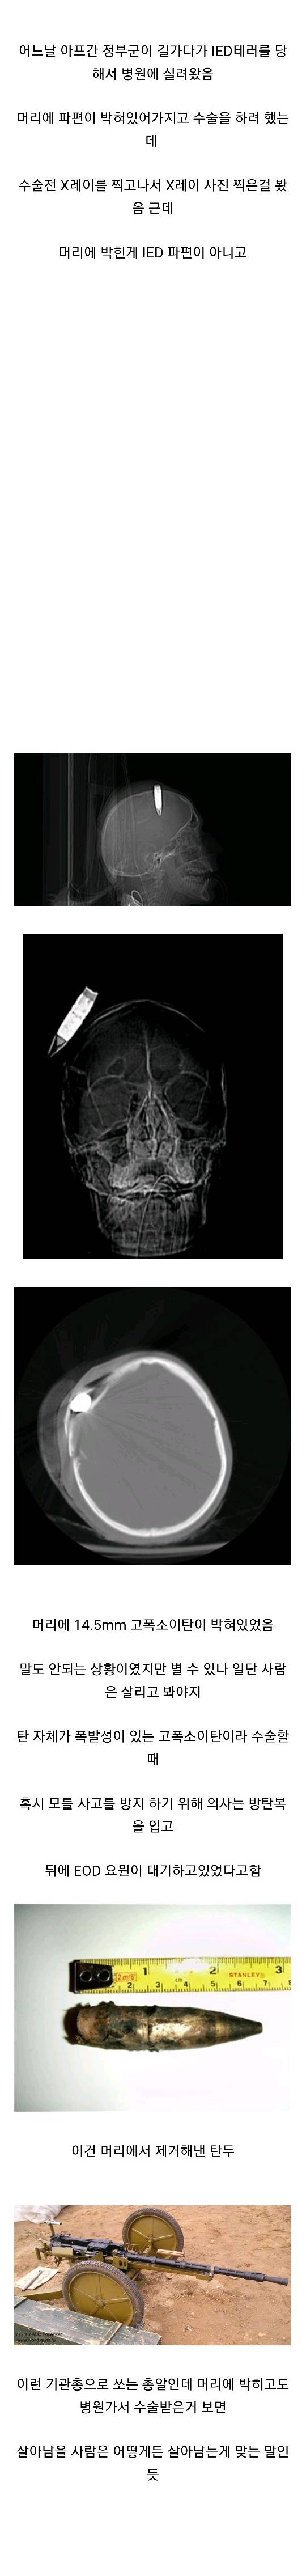

Á¦¸ñ ¾ÆÇÁ°£ ÀüÅõÁß Çìµå¼¦ ´çÇÑ ±ºÀÎ.jpg [21]